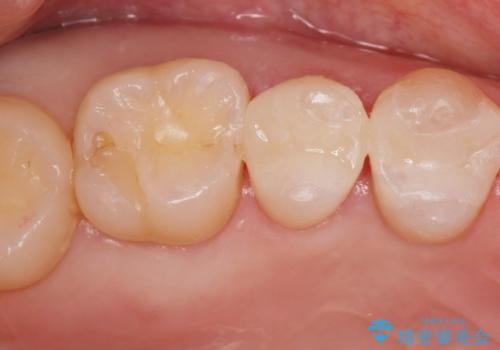

虫歯の再発リスクが高い樹脂修復部分をe-maxインレーに

- 歯と歯の間に古い樹脂の治療がされていて虫歯の再発のリスクが高まるためにe-maxインレー(セラミック)治療を行いました。

適合の良い詰め物が入りました。

セラミックは適合がよく虫歯の再発のリスクが低くなります。